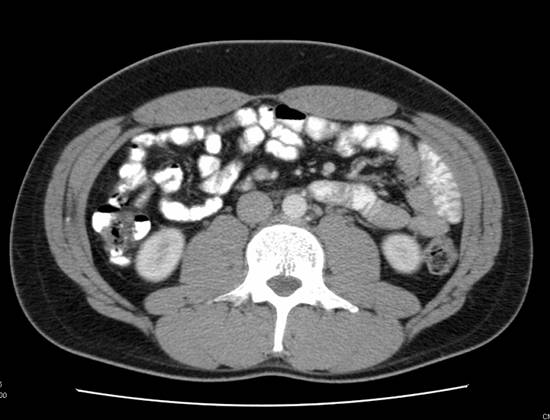

CT and PET/CT findings matched in 38 of 49 patients and where they differed, patient care had the potential to be altered in all 11 scenarios (Table 3). After being offered continued surveillance versus treatment, patients 1 and 2, both of whom had positive PET/CT and negative CT findings, elected to undergo chemotherapy. The CT scan for patient 1 had initially been read as negative. However, the PET/CT performed 14 days later identified a 2.6 cm node with increased radiotracer uptake that was visible on repeat analysis of the initial CT. The post-chemotherapy PET/CT for both patients demonstrated cessation of increased radiotracer uptake. Patient 3 had a positive CT scan with a 1.5 cm node packet adjacent to the vena cava. The PET/CT was negative, and the patient elected for surveillance. Serial CT and PET/CT examinations over the ensuing 44 months have shown stable size and finally resolution of mass at last imaging. Patient 4 had a negative CT and positive PET/CT with a 1.8 cm para-aortic lymph node (standard uptake value (SUV) 11) that could not be identified on co-registered CT images. He elected to undergo chemotherapy and subsequently had normalization of PET images in this area and no future recurrence. Patient 5 had a positive CT and CT/PET for a stage III NSGCT. After receiving chemotherapy the CT remained positive demonstrating a 1.5cm retroperitoneal LN and the PET/CT was negative for metabolic activity. Subsequent RPLND revealed fibrosis only. Patient 6 had a negative CT and a positive PET/CT obtained 18 days later. This scan revealed a 1.5cm pre-aortic and a 2.5cm left psoas lymph node, SUV's for both were 16. Again, as in Patient 1, review of the original CT indicated presence of these nodes. The patient received chemotherapy and had normalization of imaging subsequently. Patient 7 had a Stage I NSGCT with negative CT and positive PET/CT indicating 1.2 and 0.9cm (SUV 3.6) lymph nodes on initial evaluation. He underwent observation and his tumor markers began to rise 2 months after his PET/CT. Repeat CT was still negative. He underwent chemotherapy with resolution of all findings. Patient 8 had Stage I NSGCT and initial CT indicating multiple groups of equivocal lymph nodes (each approximately 1cm) consistent with metastatic disease. His PET/CT and subsequent RPLND were negative. Patient 9 had stage IIIa NSGCT and subsequent chemotherapy. His post-treatment imaging revealed 2 nodes slightly greater than 1.0cm, and his PET/CT was negative. RPLND revealed fibrosis. Patient 10 initially presented with stage I NSGCT, his CT was negative but CT/PET revealed an 8mm para-aortic lymph node (SUV 3.25) (Figure 1). Subsequent RPLND confirmed this to be positive with a mixture of embryonal and teratomatous components. Patient 11 initially presented with Stage IIa NSGCT, his CT and PET/CT at the time of presentation confirmed two para-aortic lymp nodes 2.29 and 2.10cm (SUV 17). Chemotherapy was administered and subsequent imaging noted no significant decrease in size of these nodes but they were not metabolically active on PET/CT. Subsequent RPLND revealed fibrosis.Three patients in our series had evidence of masses both on CT and PET/CT with teratoma on pathologic examination of the RPLND specimens. It should be noted that in none of these cases was the mass metabolically active, with maximum SUV being 2.2. Of the 12 patients that underwent chemotherapy after a positive PET/CT, all had a repeat PET/CT following chemotherapy which was negative.

Figure 1

A (top image): CT image demonstrating an absence of lymph node enlargement in Patient 10. B (bottom image): Analogous PET/CT image with arrow indicating site of increased FDG metabolism.